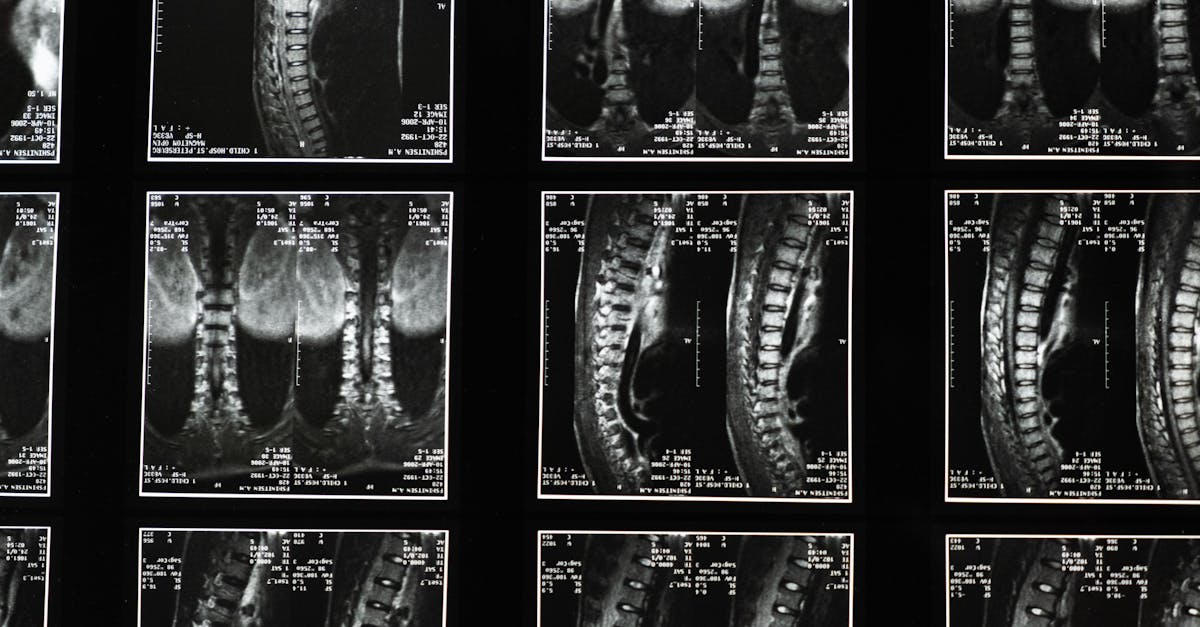

Lorsqu’un disque intervertébral est endommagé, il peut exercer une pression sur les racines nerveuses adjacentes, entraînant des douleurs aiguës qui peuvent irradier dans les membres. La décompression neurovertébrale agit en réduisant cette pression par des mécanismes de traction douce appliqués sur la colonne. Ce processus crée un « effet de vide » qui non seulement repositionne les disques déplacés, mais favorise également la circulation sanguine et la nutrition des tissus. Cela permet une réparation plus rapide et un retour à une fonction normale.

En ciblant directement les racines nerveuses déformées, la décompression neurovertébrale soulage efficacement la pression faite sur les disques intervertébraux. Cela permet de favoriser un meilleur environnement pour la guérison et la régénération des tissus endommagés. En créant un effet de ‘vide’ au sein des vertèbres, cette technique aide à repositionner les disques déplacés et à réduire l’inflammation qui pourrait aggraver la situation.